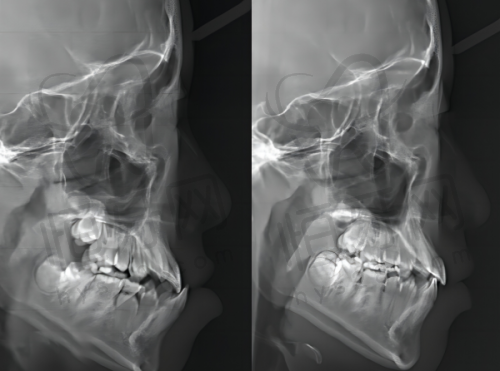

我在四川乐山安普口腔门诊看病,医生告诉我需要治疗地包天。首先,我走进诊室,医生微笑着让我坐下。他先用牙镜仔细检查我的牙齿,发现我的上牙和下牙咬合不正。接着,医生给我讲解了地包天的情况,告诉我需要矫正。然后,医生开始进行拍片,拍摄了我的牙齿和颌骨的光片。医生认真分析了片子,告诉我需要佩戴矫正器。接着,医生为我设计了个性化的矫正方案,详细说明了每一步的治疗过程。随后,医生开始为我安装矫正器。他先用专用工具清洁我的牙齿,确保没有任何杂质。接着,医生小心翼翼地将矫正器固定在我的牙齿上,整个过程非常细致。安装完成后,医生让我在镜子前查看结果,确认无误后,医生给我讲解了佩戴矫正器的注意事项。后,医生安排了定期复诊的时间,确保我在治疗期间能够得到及时的调整和指导。我心里想着,虽然过程有点复杂,但为了矫正我的地包天,我愿意坚持下去。